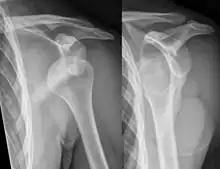

A diagnosis of shoulder dislocation is often suspected based on the person's history and physical examination. Radiographs are made to confirm the diagnosis. Most dislocations are apparent on radiographs showing incongruence of the glenohumeral joint. Posterior dislocations may be hard to detect on standard AP radiographs, but are more readily detected on other views. After reduction, radiographs are usually repeated to confirm successful reduction and to detect bone damage. After repeated shoulder dislocations, an MRI scan may be used to assess soft tissue damage. In regards to recurrent dislocations, the apprehension test (anterior instability) and sulcus sign (inferior instability) are useful methods for determining predisposition to future dislocation.

Anterior dislocation of the right shoulder. AP X ray

Anterior dislocation of the right shoulder. Y view X ray.